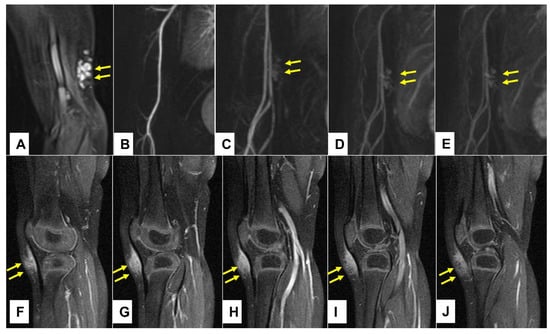

Figure 9.

This composite figure illustrates the typical imaging differences between the low-flow subcutaneous vascular malformations (SVM) and subcutaneous granuloma annulare (SGA) as seen on the MR images. In images (A–D), four patients with multicystic subcutaneous lesions pointed out by yellow arrows are presented. These lesions were accurately diagnosed by MRI and after excision, also confirmed by histopathology as a venous malformation on the left knee in an 11-year-old boy (A); venous malformation on the right upper arm in a 4-year-old boy (B); lymphatic malformation on the right elbow in a 4-year-old girl (C); lymphatic malformation on the left upper arm in an 8-year-old girl (D). In images (E–H), four patients with homogenous subcutaneous lesions marked with 3 yellow arrows each are presented. These lesions remained inconclusive after MRI, with the main differential diagnosis being the low-flow SVM in all cases. Because malignancy could not be excluded, surgical biopsy was needed, and the diagnosis of SGA was confirmed by histopathology in all cases. (E) right knee in a 2.5-year-old boy, (F) right lower leg in a 3-year-old girl, (G) left forearm in a 4-year-old boy, (H) left foot in a 3-year-old girl. Note that all SVM have a cystic appearance on the MRI, whereas SGA shows the typical epifascial extension with gradual rise of the lesion towards the more superficial tissues, which we have named the “epifascial cap” sign. These self-limiting lesions show a homogenous appearance in the MRI and do not invade the fascia.